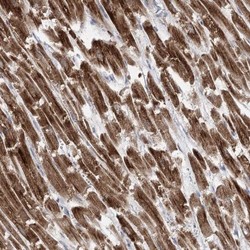

- Immunohistochemistry-Paraffin: Pyruvate Dehydrogenase E1 beta subunit Antibody [NBP1-87421] - Staining of human heart muscle shows high expression.